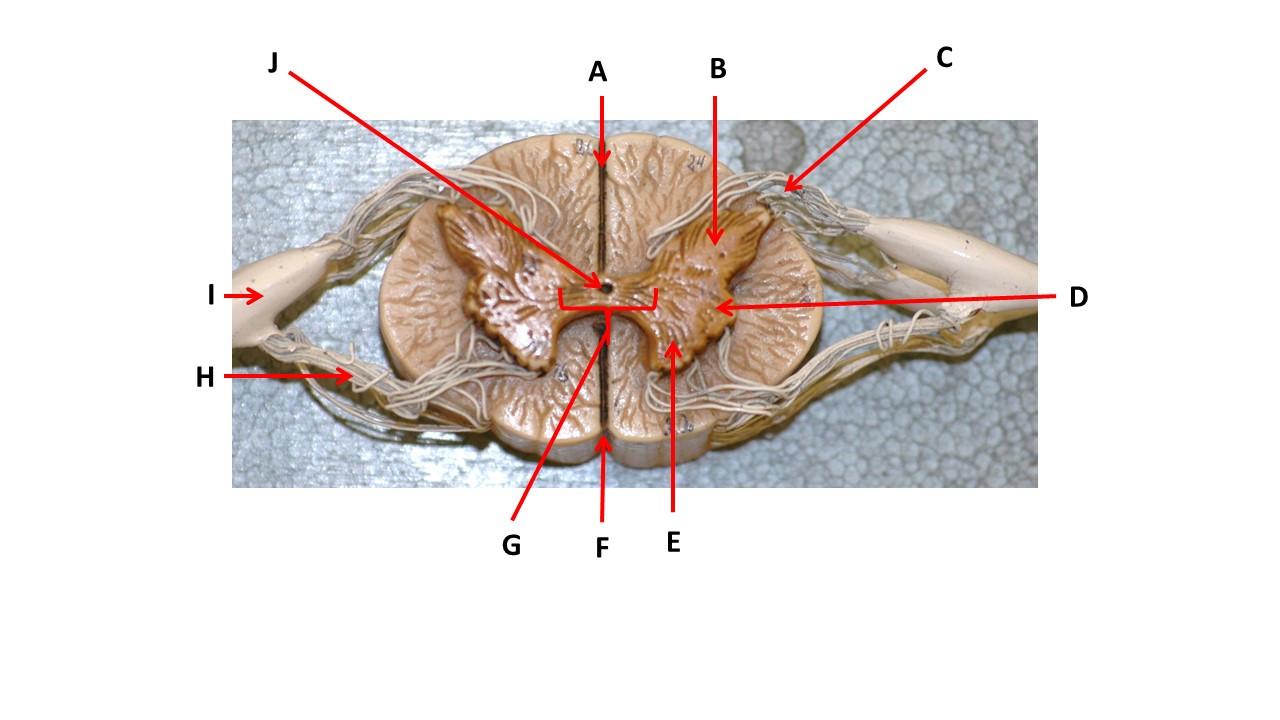

Name the region of tissue surrounding the tip of arrow E.

Name the region of tissue surrounding the tip of arrow B.

Name the region of tissue surrounding the tip of arrow J.

Name the region of tissue surrounding the tip of arrow E.

lateral horn

Name the region of tissue surrounding the tip of arrow N.

dorsal column

Which structure(s ) would be found in the area at the tip of arrow D.

cell bodies of interneurons

Name the region of tissue surrounding the tip of arrow E.

ventral horn

Name the region within bracket G.

gray commisure